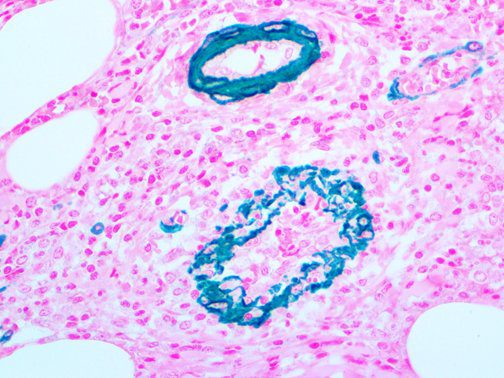

This activation induces inflammatory monocytes to highly express IL-6, starting a localized and then systemic cascade effect that results in hyperproduction of IL-6, which accelerates the inflammatory process. Because IL-6 also increases vascular permeability, excessive levels cause blood vessels to become very leaky. This, along with clotting factors released from vascular endothelial cells, stimulates the coagulation cascade, resulting in microthrombosis (tiny clots), which leads to ischemia and tissue death of the kidney, intestines, heart, liver, brain and extremities.